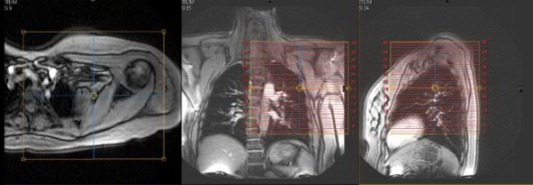

| AXIAL | T1 | TSE | 4mm | 1mm | None | 20cm | Cover entire scapula |

| AXIAL | T2 Fat Sat (TE=50-60) | TSE | 4mm | 1mm | SPAIR | 20cm | Cover entire scapula |

| SAG | T1 | TSE | 4mm | 1mm | None | 22cm | Perpendicular to scapula |

| SAG | T2 Fat Sat (TE=50-60) | TSE | 4mm | 1mm | SPAIR | 22cm | Perpendicular to scapula |

| COR | STIR | TSE | 4mm | 1mm | STIR | 25cm | Parallel to scapula |